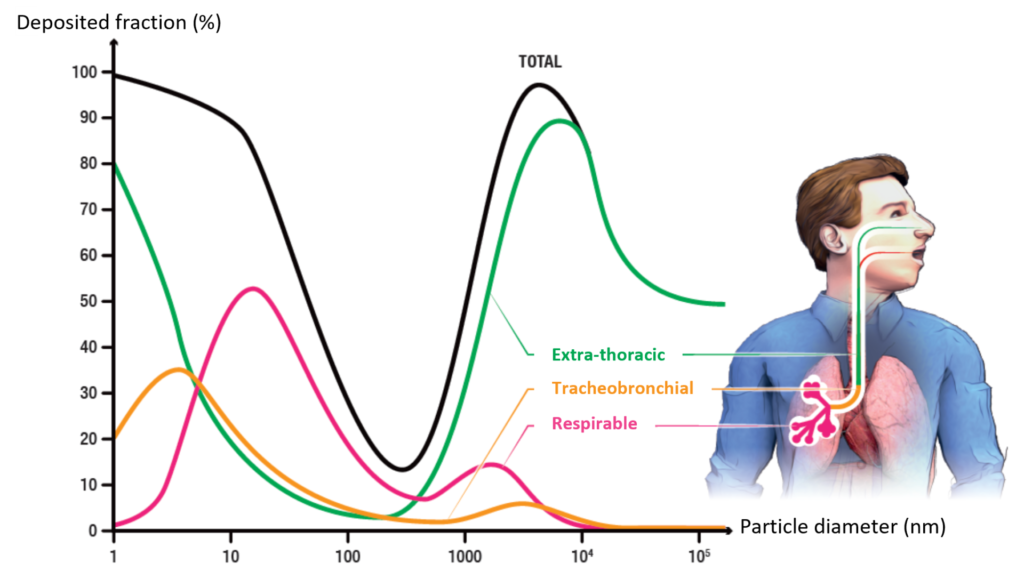

Deposition of particles along the respiratory tree is guided by their size. Particles between 10 nm and 100 nm are mainly distributed in the alveolar region.

After inhalation, some particles may migrate to:

- The blood

- The lymphatic system

- Brain structures

- The pleura

- Other viscera (liver, spleen)

The main effects are:

- Increased overall mortality

- Increased mortality from respiratory and cardiovascular causes

- Impairment of lung and heart function

- Pulmonary inflammatory effects

- Disruption of blood coagulation